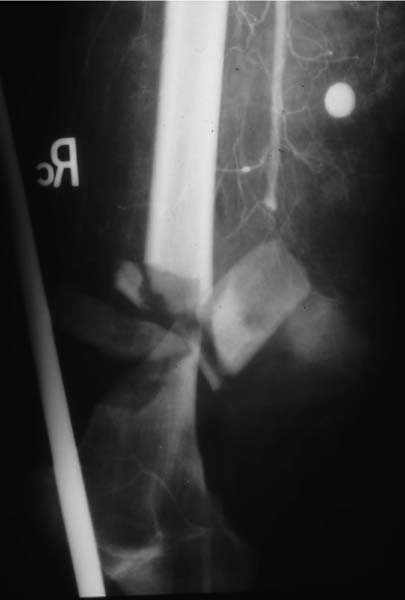

Case 1 - comminuted open supracondylar fx femur, no pulses, huge hematoma and bleeding. The angio shows popliteal artery transection. Immediately taken to OR where proximal and distal control are obtained prior to shunting. THEN Ortho ex-fixes the joint. The artery is definitively repaired. The wound is debrided. Later Ortho does a definitive ORIF with bone graft - successful.

Shunt